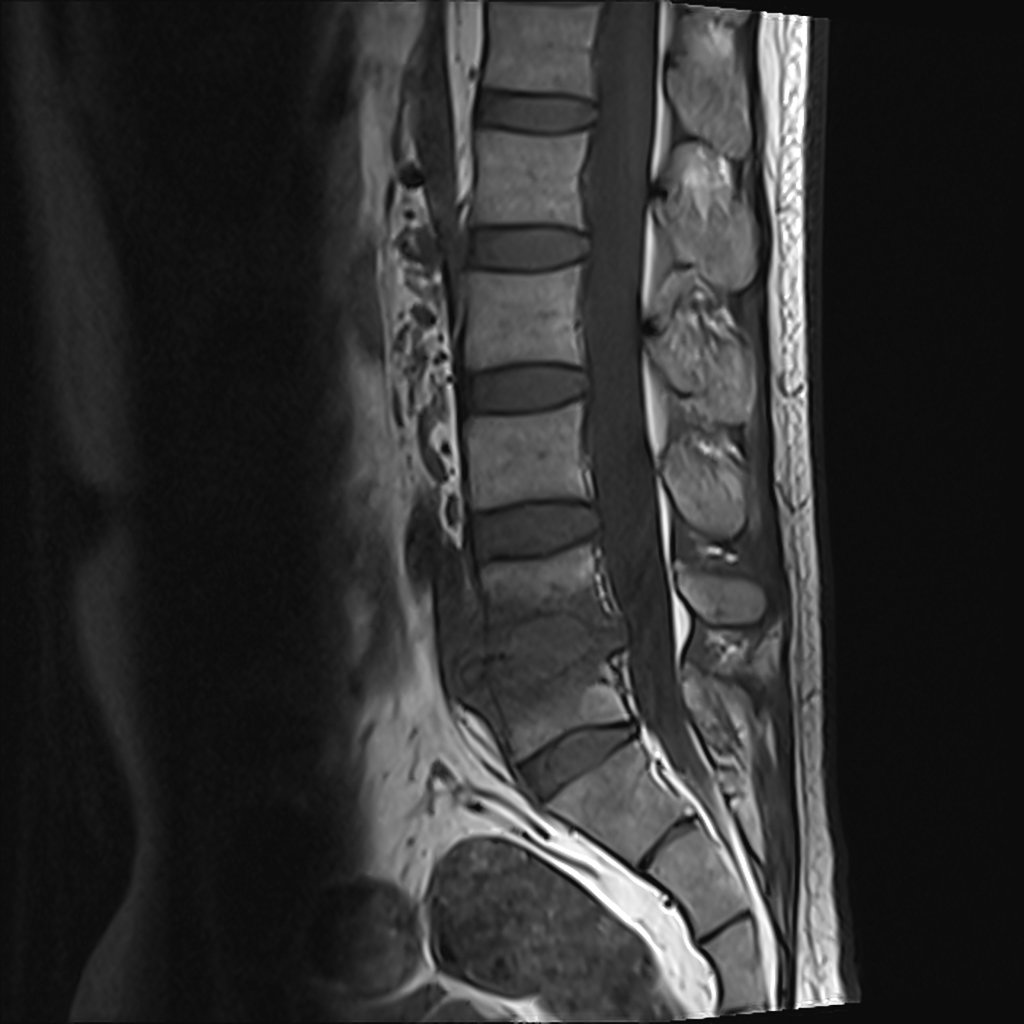

Lumbosacraal radiculair syndroom =

"Uitstralende pijn in één bil of been, al dan niet met andere prikkelingsverschijnselen en neurologische uitvalsverschijnselen, die suggestief is voor een prikkeling van één (of twee) specifieke lumbosacrale zenuwwortel(s)"2

Beeldvorming

• NHG (2015) NA 6 weken in samenspraak met patiënt2